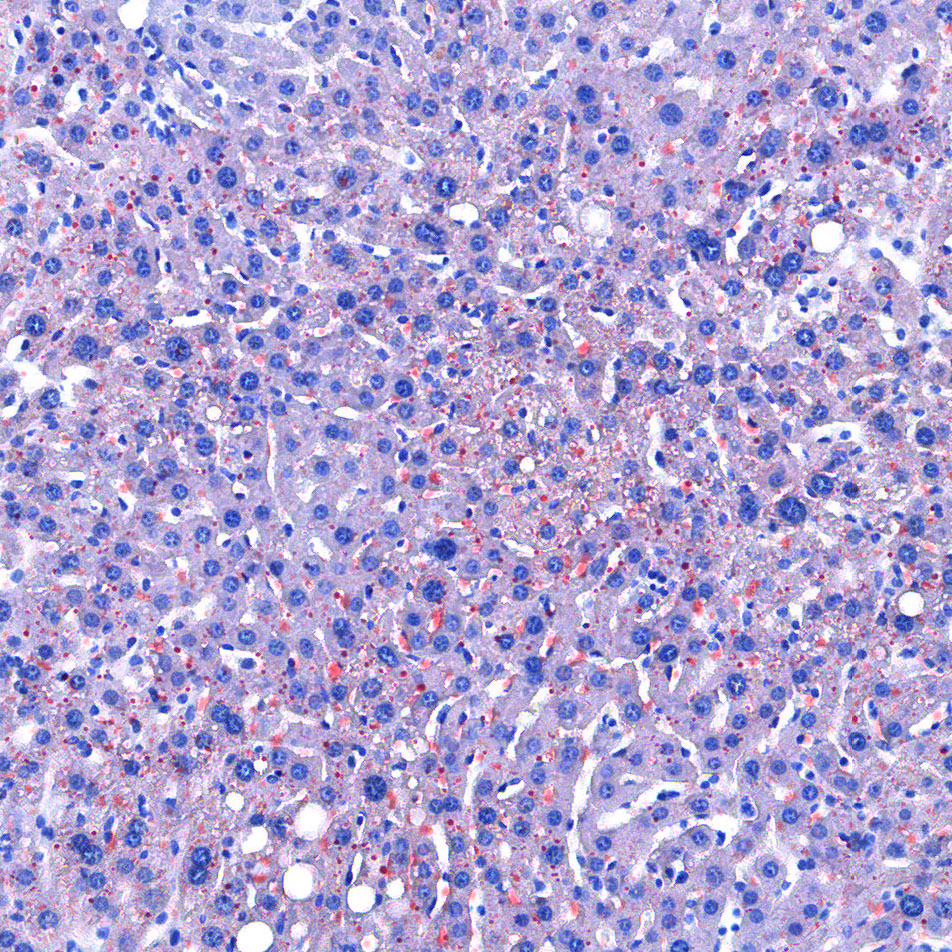

油红O染色

油红O对脂滴的染色机制一般认为是物理学上的溶液作用或吸附作用,借溶液作用使脂质染色,即油红O先溶于60%异丙醇中,然后切片浸入油红O染液中时,油红O在组织脂质的溶解度较60%异丙醇中的溶解度高,所以在染色时油红O从60%异丙醇中转移入脂质中使脂滴显示红色。

实验结果展示:

油红O-肝>